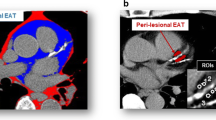

As shown in Table 3, the coronary TBR was significantly correlated with the PCAT density (r = 0.56, P < .001). There were significant correlations between the TBR value and the corresponding PCAT density in LAD, LCX, and RCA territories (r = 0.47, P < .001; r = 0.36, P < .001; r = 0.41, P < .001; respectively) (Figure 4). Per patient, we found that the PCAT density was independently associated with the coronary TBR (Beta: 0.448 per SD increase; 95% confidence interval: 0.286-0.610; P < .001) by multiple linear regression analysis (age, sex, body-mass index as covariates). After adjustment for SYNTAX score and coronary artery calcium score, the PCAT density was also independently associated with the coronary TBR (Beta: 0.416 per SD increase; 95% confidence interval: 0.222-0.610; P < .001). Significant associations were found after adjustment for combined cardiac risk factors and serum biomarkers (Table 4). Representative images are illustrated for PCAT and TBR in Figure 5.

Correlations between the PCAT and the coronary TBR. Scatterplots of PCAT vs TBR (A), PCATLAD vs TBRLAD (B), PCATLCX vs TBRLCX (C), PCATRCA vs TBRRCA (D). r, spearman correlation coefficients; LAD, left anterior descending; LCX, left circumflex; PCAT, peri-coronary adipose tissue; RCA, right coronary artery; TBR, tissue-to-background ratio

Representative case showing the relationship between the coronary TBR with the PCAT in a patient with prominent 18F-NaF uptake. Patient (male; 64 years) suffered multivessel lesions presenting intense focal 18F-NaF uptake in LAD (A, B), LCX (E, F), RCA (I, J). Epicardial adipose area (green) for placing five regions of interest (3 mm2) and measuring PCAT density surrounding the LAD (C, D), LCX (G, H), RCA (K, L). 18F-NaF, 18F-sodium fluoride; LAD, left anterior descending; LCX, left circumflex; PCAT, peri-coronary adipose tissue; RCA, right coronary artery; TBR, tissue-to-background ratio